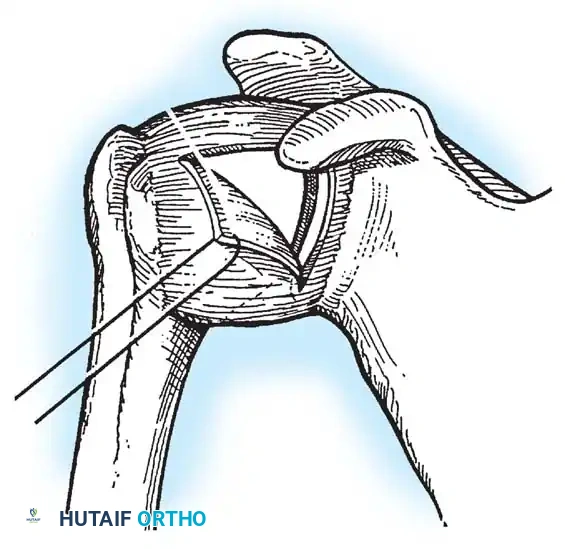

Capsulotomy and Joint Inspection

A vertical or T-shaped capsulotomy is performed based on the degree of capsular laxity and the planned shift.

- For a standard Bankart repair with an inferior capsular shift, a vertical incision is made 1 cm medial to the humeral articular margin. A horizontal limb can be added to create superior and inferior capsular flaps.

- Tagging sutures are placed in the capsular flaps for traction.

- A Fukuda retractor is placed within the joint to retract the humeral head laterally and posteriorly, exposing the anterior glenoid rim and labrum.

Glenoid Preparation and Labral Repair

The essential step in restoring stability is the anatomical reduction of the capsulolabral complex to a bleeding bone bed on the anterior glenoid rim.

- Debridement: The anterior glenoid neck is decorticated using a motorized burr, rasp, or osteotome to create a bleeding cancellous bed. This promotes robust biological healing of the repaired labrum.

- Mobilization: The scarred, medially displaced labrum (ALPSA lesion) must be fully mobilized using a periosteal elevator until the subscapularis muscle belly is visible anteriorly. The tissue must float freely to be shifted superiorly and laterally.

- Anchor Placement: Suture anchors (typically 3 to 4) are placed along the articular margin of the anteroinferior glenoid (from the 5:30 to 3:00 positions for a right shoulder). Anchors must be inserted at a 45-degree angle to the articular surface to maximize pullout strength and avoid joint penetration.

Capsular Shift and Closure

To address capsular redundancy, an inferior capsular shift is performed.

- The arm is positioned in 30 to 45 degrees of abduction and 20 degrees of external rotation.

- The inferior capsular flap is advanced superiorly and laterally, tensioning the IGHL complex. The sutures from the anchors are passed through the shifted capsule and tied.

- The superior flap is then brought down over the inferior flap in a "pants-over-vest" fashion to reinforce the anterior wall and close the rotator interval.